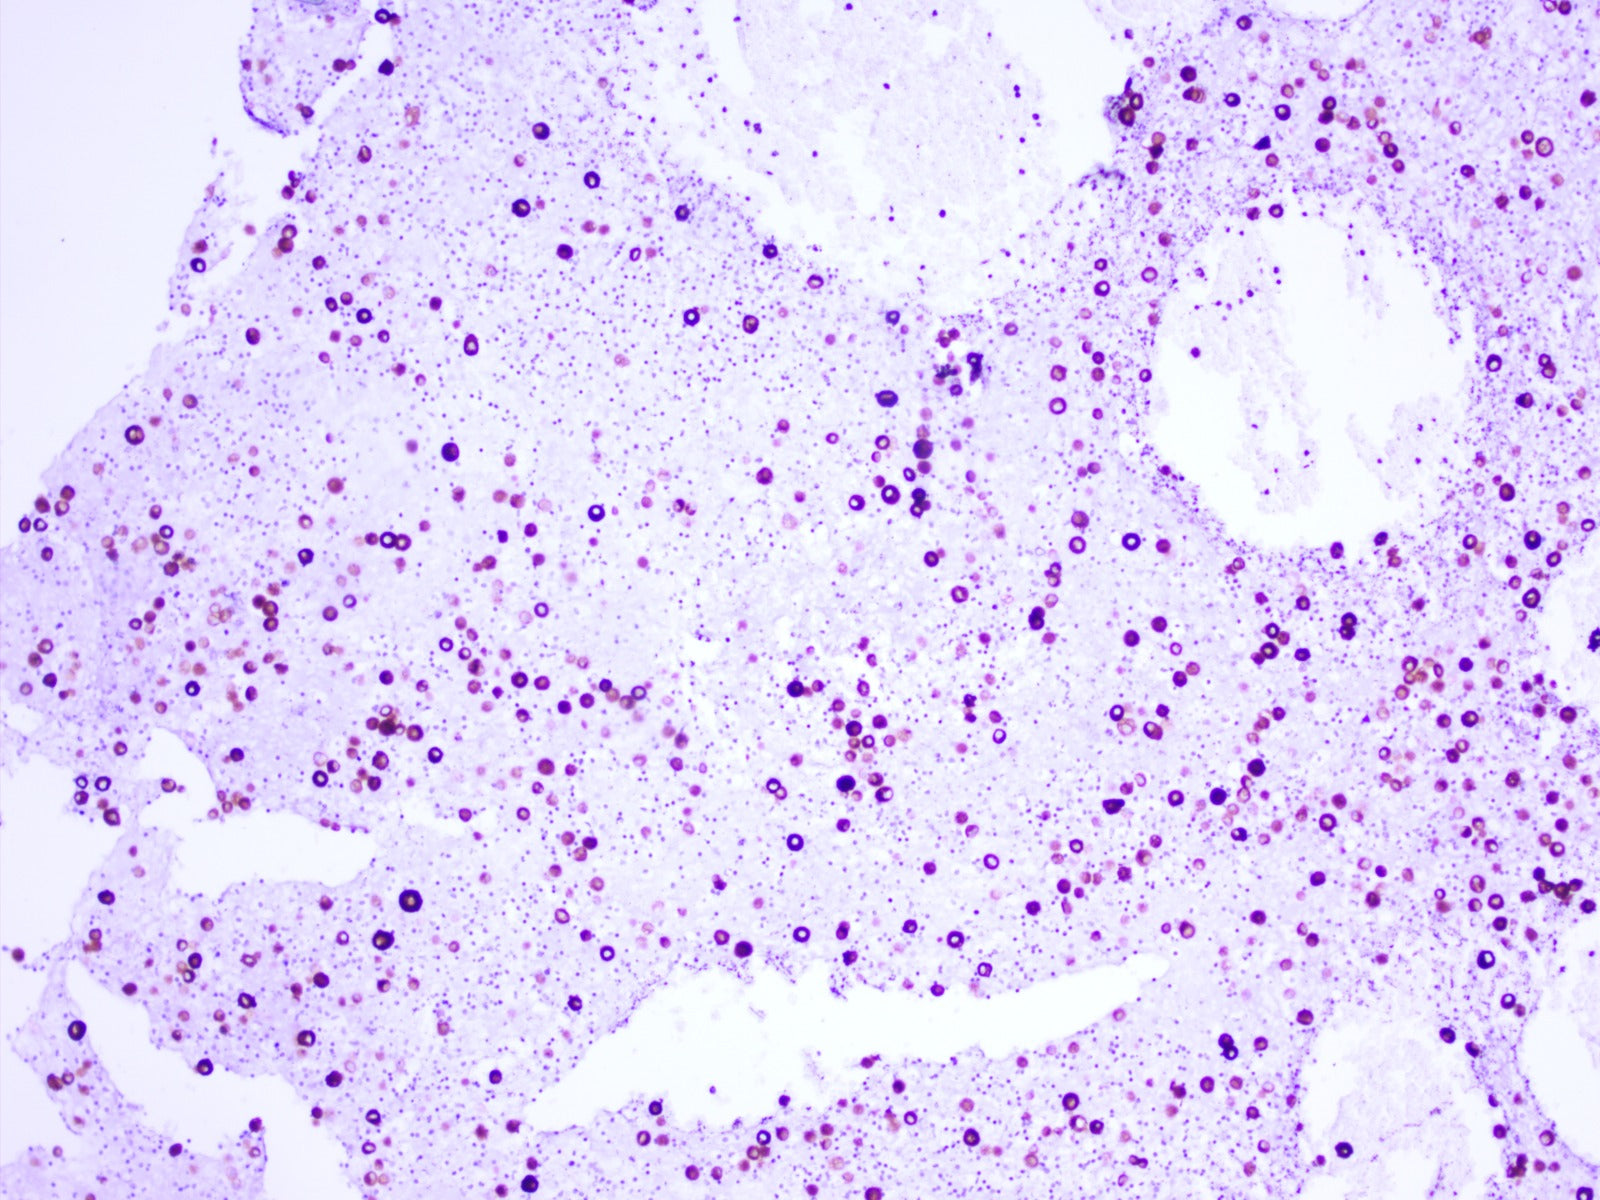

Staining Photos:

Mouse spleen – SMA-1%-PEG: